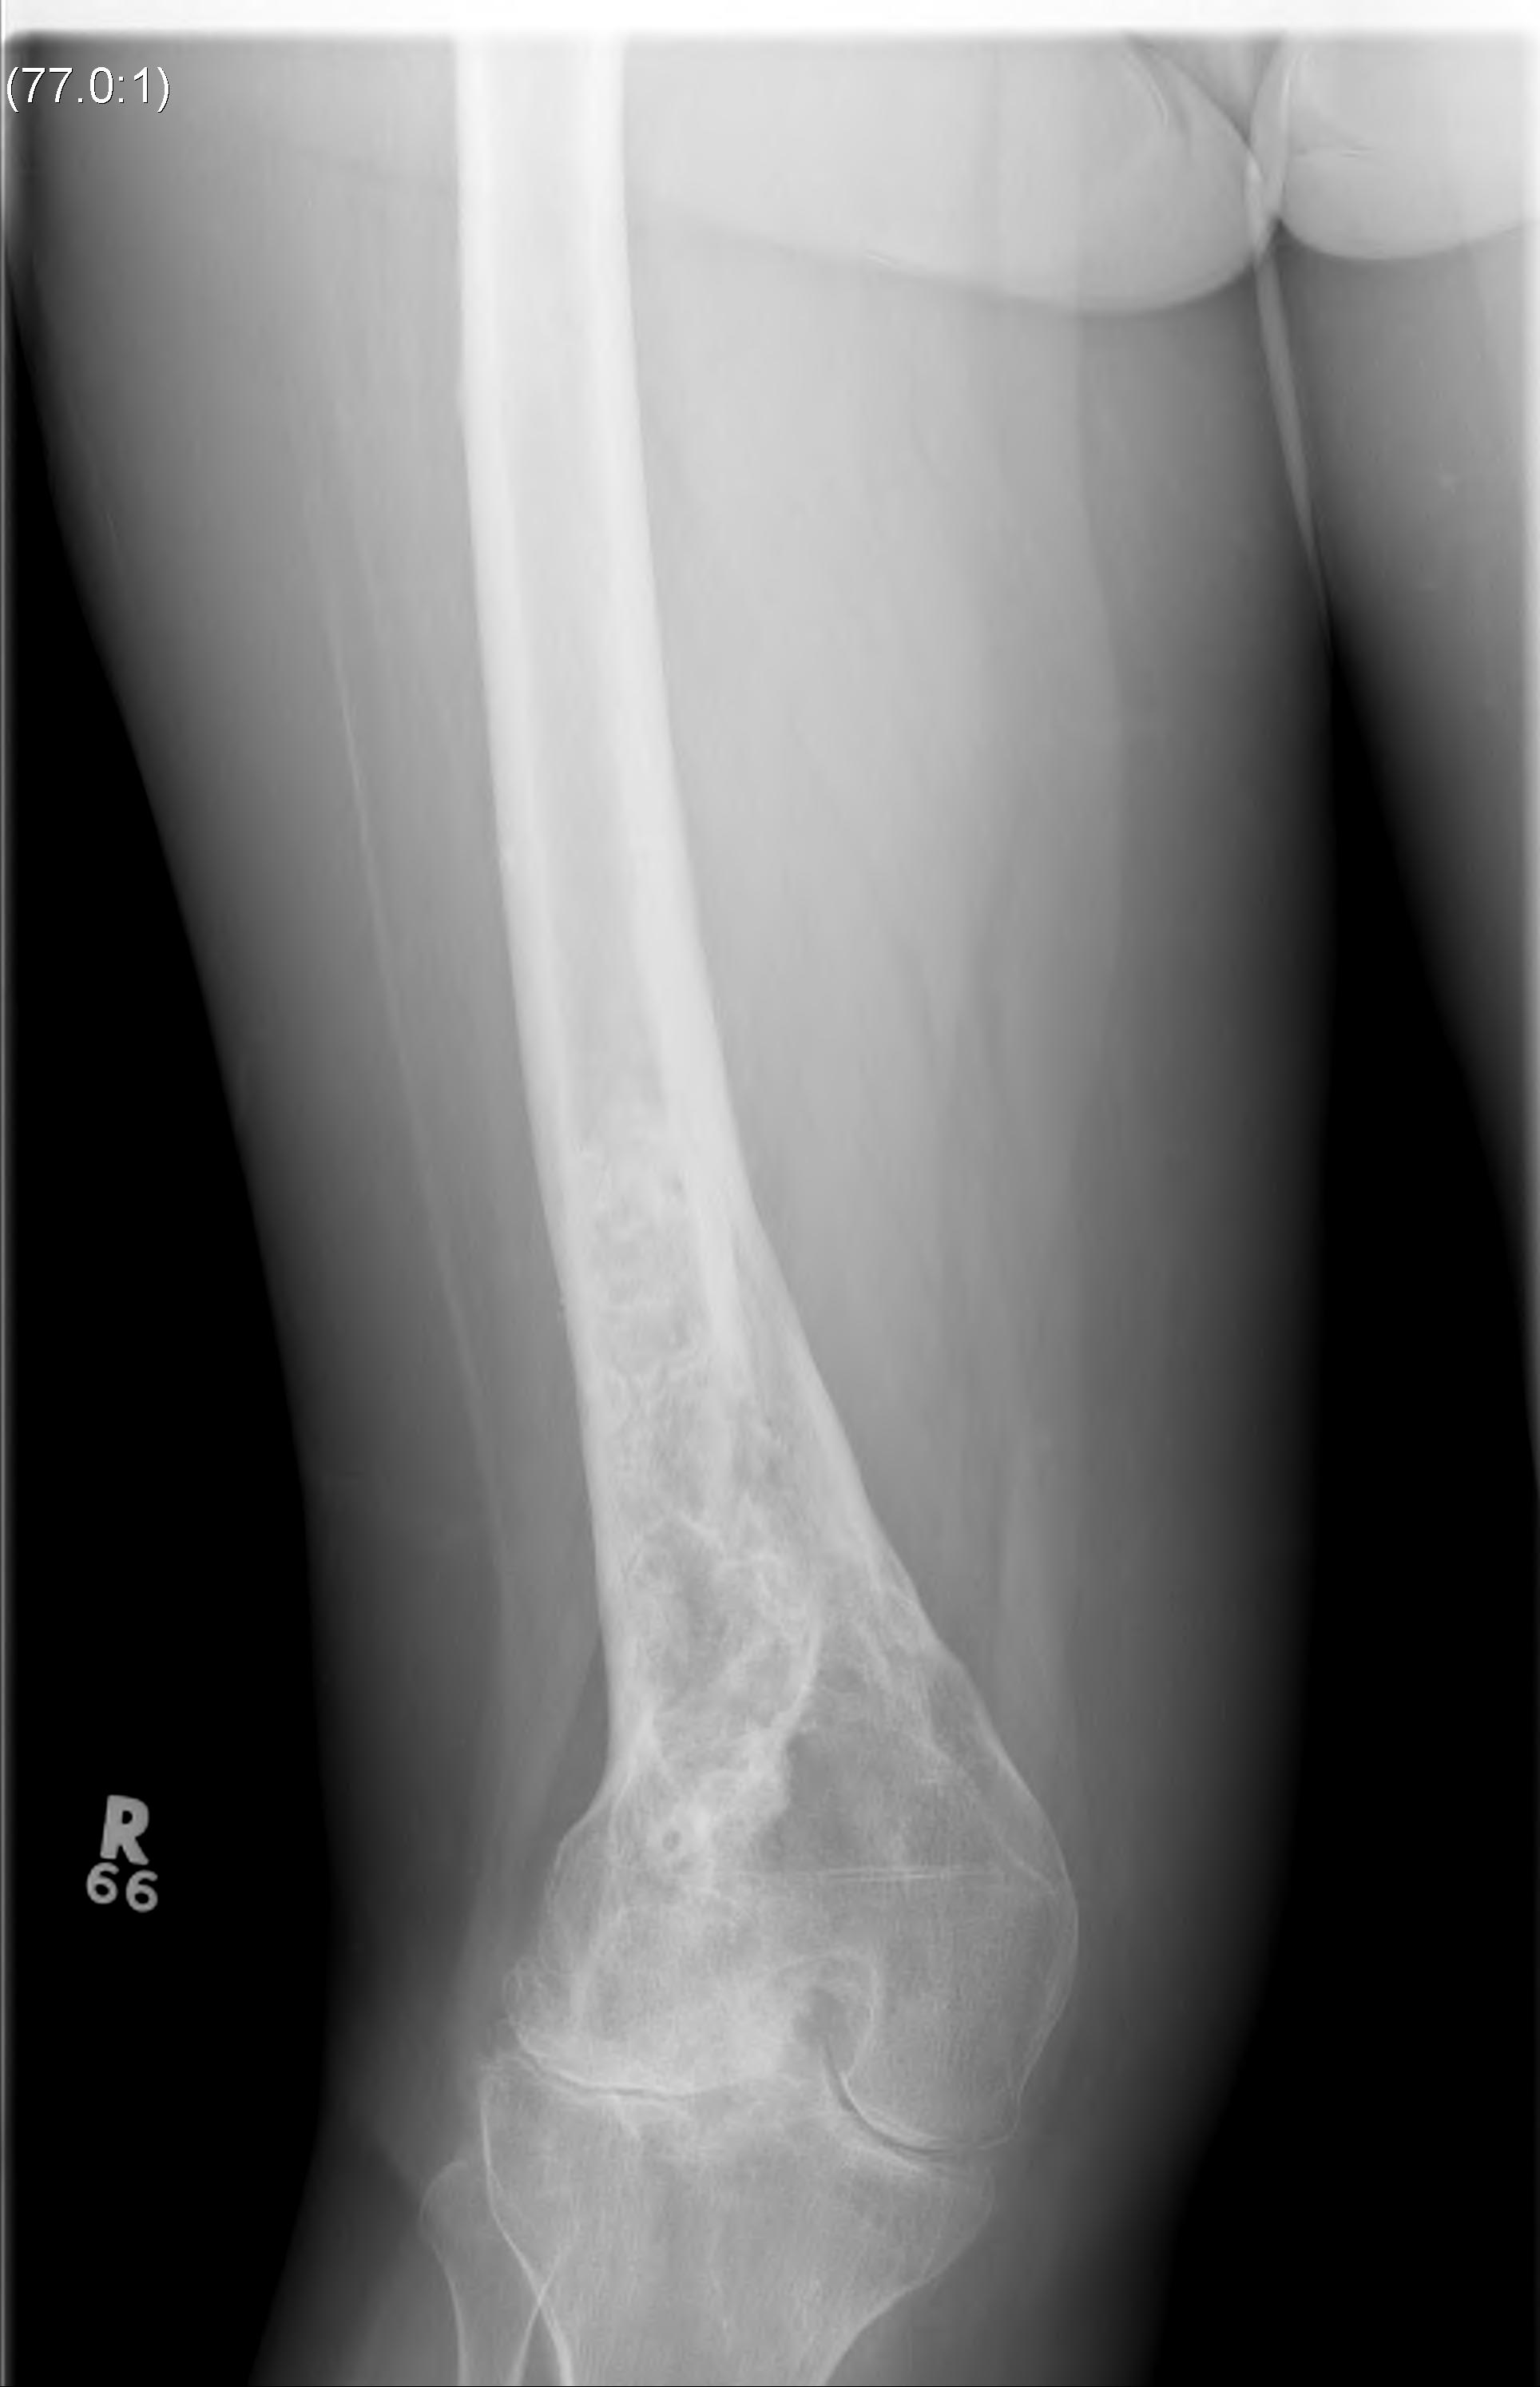

Paget's

Fracture Malunion